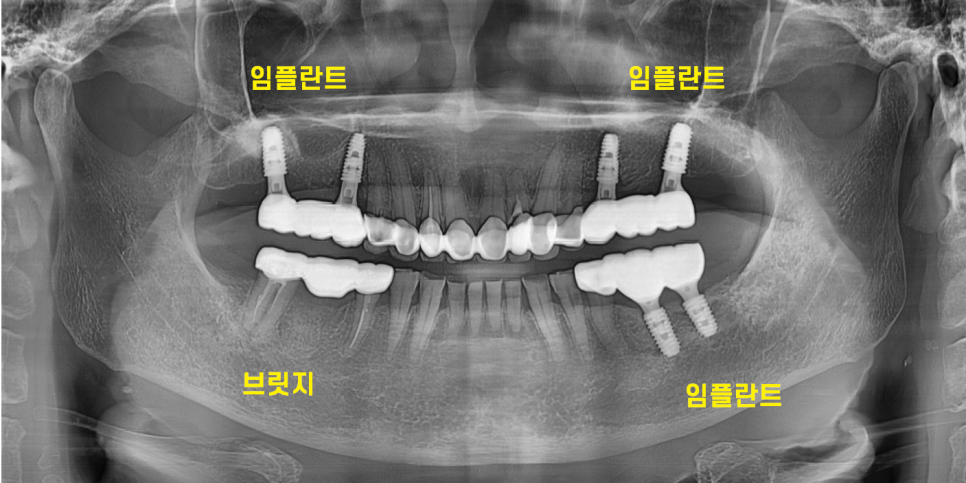

240202

딱 5번 내원하셔서 치료를 끝내드렸습니다.

상담

왼쪽 수술

오른쪽 수술

인상채득

보철 부착

24.2.2

이가없던 위 어금니도

문제가 있던 아래 어금니도

문제가 있는 부분 싹 고쳐드렸습니다.